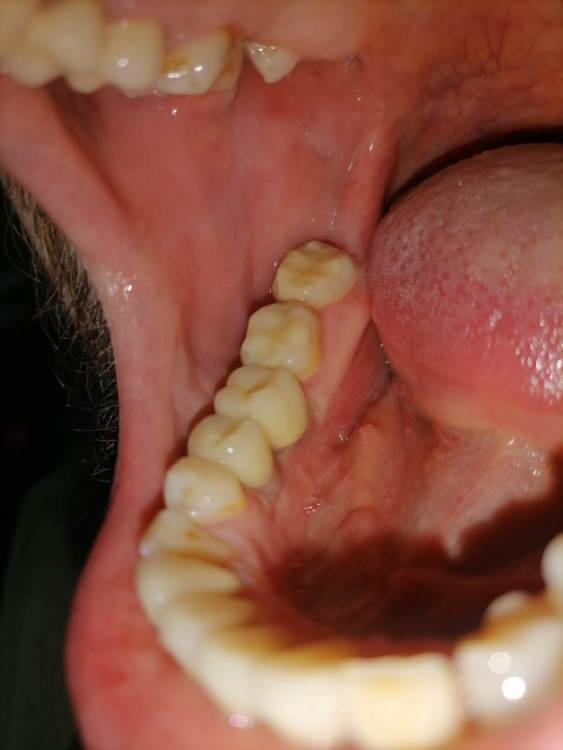

Добрый день уважаемые доктора. После установки коронок на импланты, беспокоит что на контрольном снимке оголилось 2 витка резьбы импланта.

Сами импланты установлены в ноябре.  Коронки на них поставили месяц  назад, закрутили с усилием 25 ньютонов, и поставили временную пломбу . Отправили на месяц гулять. Сегодня сделал снимок, пришёл к врачу врач сказала что все отлично. Докрутила на 35 и поставила постоянную пломбу. Но меня беспокоит что ушло несколько витков резьбы, хотелось бы услышать ваше мнение, скажите это нормально? По ощущениям ничего не беспокоит, жую без проблем.